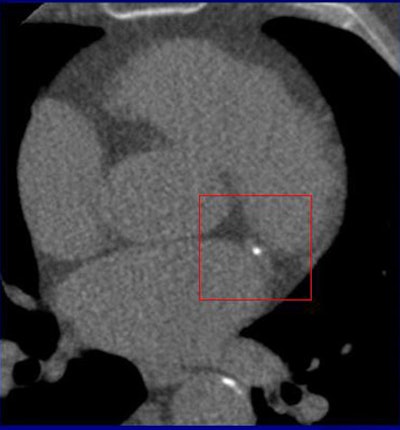

![]() |

| CT calcium scoring was performed on a 69-year-old man on daily beta-blocker medication. The patient's mean heart rate was 49 during the scan. The Agatston score throughout the 10 phases ranged from 710 to 986, with a score of 973 in the most-motionless (70% RR interval) phase. All images courtesy of Dr. Annemarieke Rutten. |